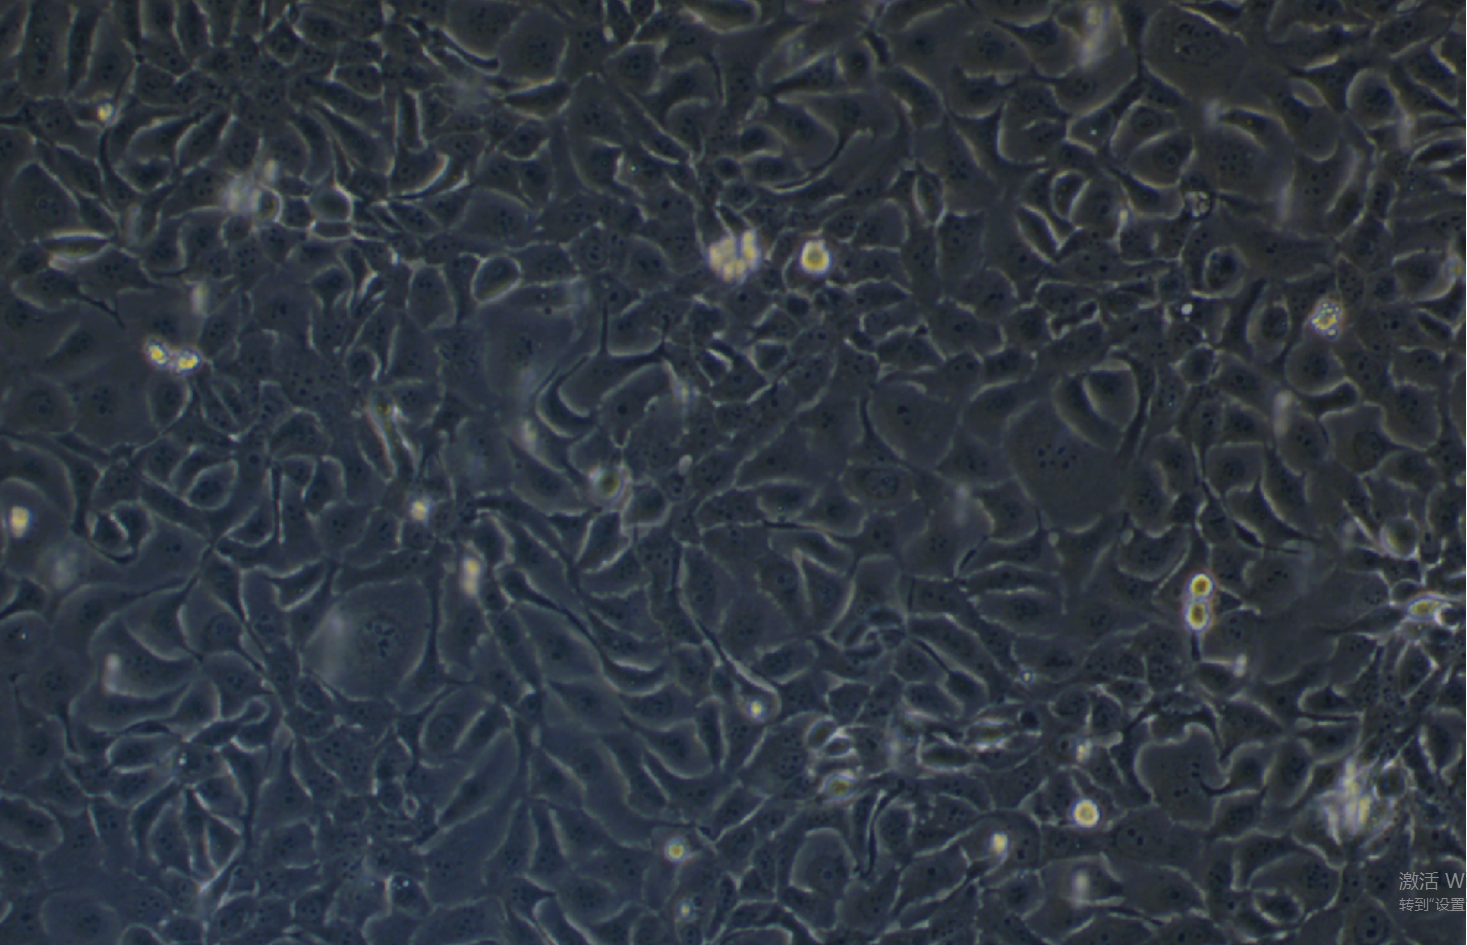

形態 |

上皮細胞樣 |

生長特征 |

貼壁生長 |